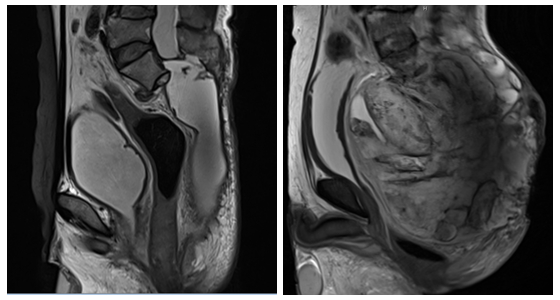

手术前后对比图

手术当天,孙志华主任团队进行麻醉及术中保障。手术采用后入路,术中患者俯卧位。逐层切开皮肤和筋膜显露骶骨,进入椎管分离神经并保护,向腹侧向头端游离肿瘤,这个过程相当关键,必须看清肠道、血管等组织结构,不能有一点点损伤……最终骶骨巨大脊索瘤完整切除。